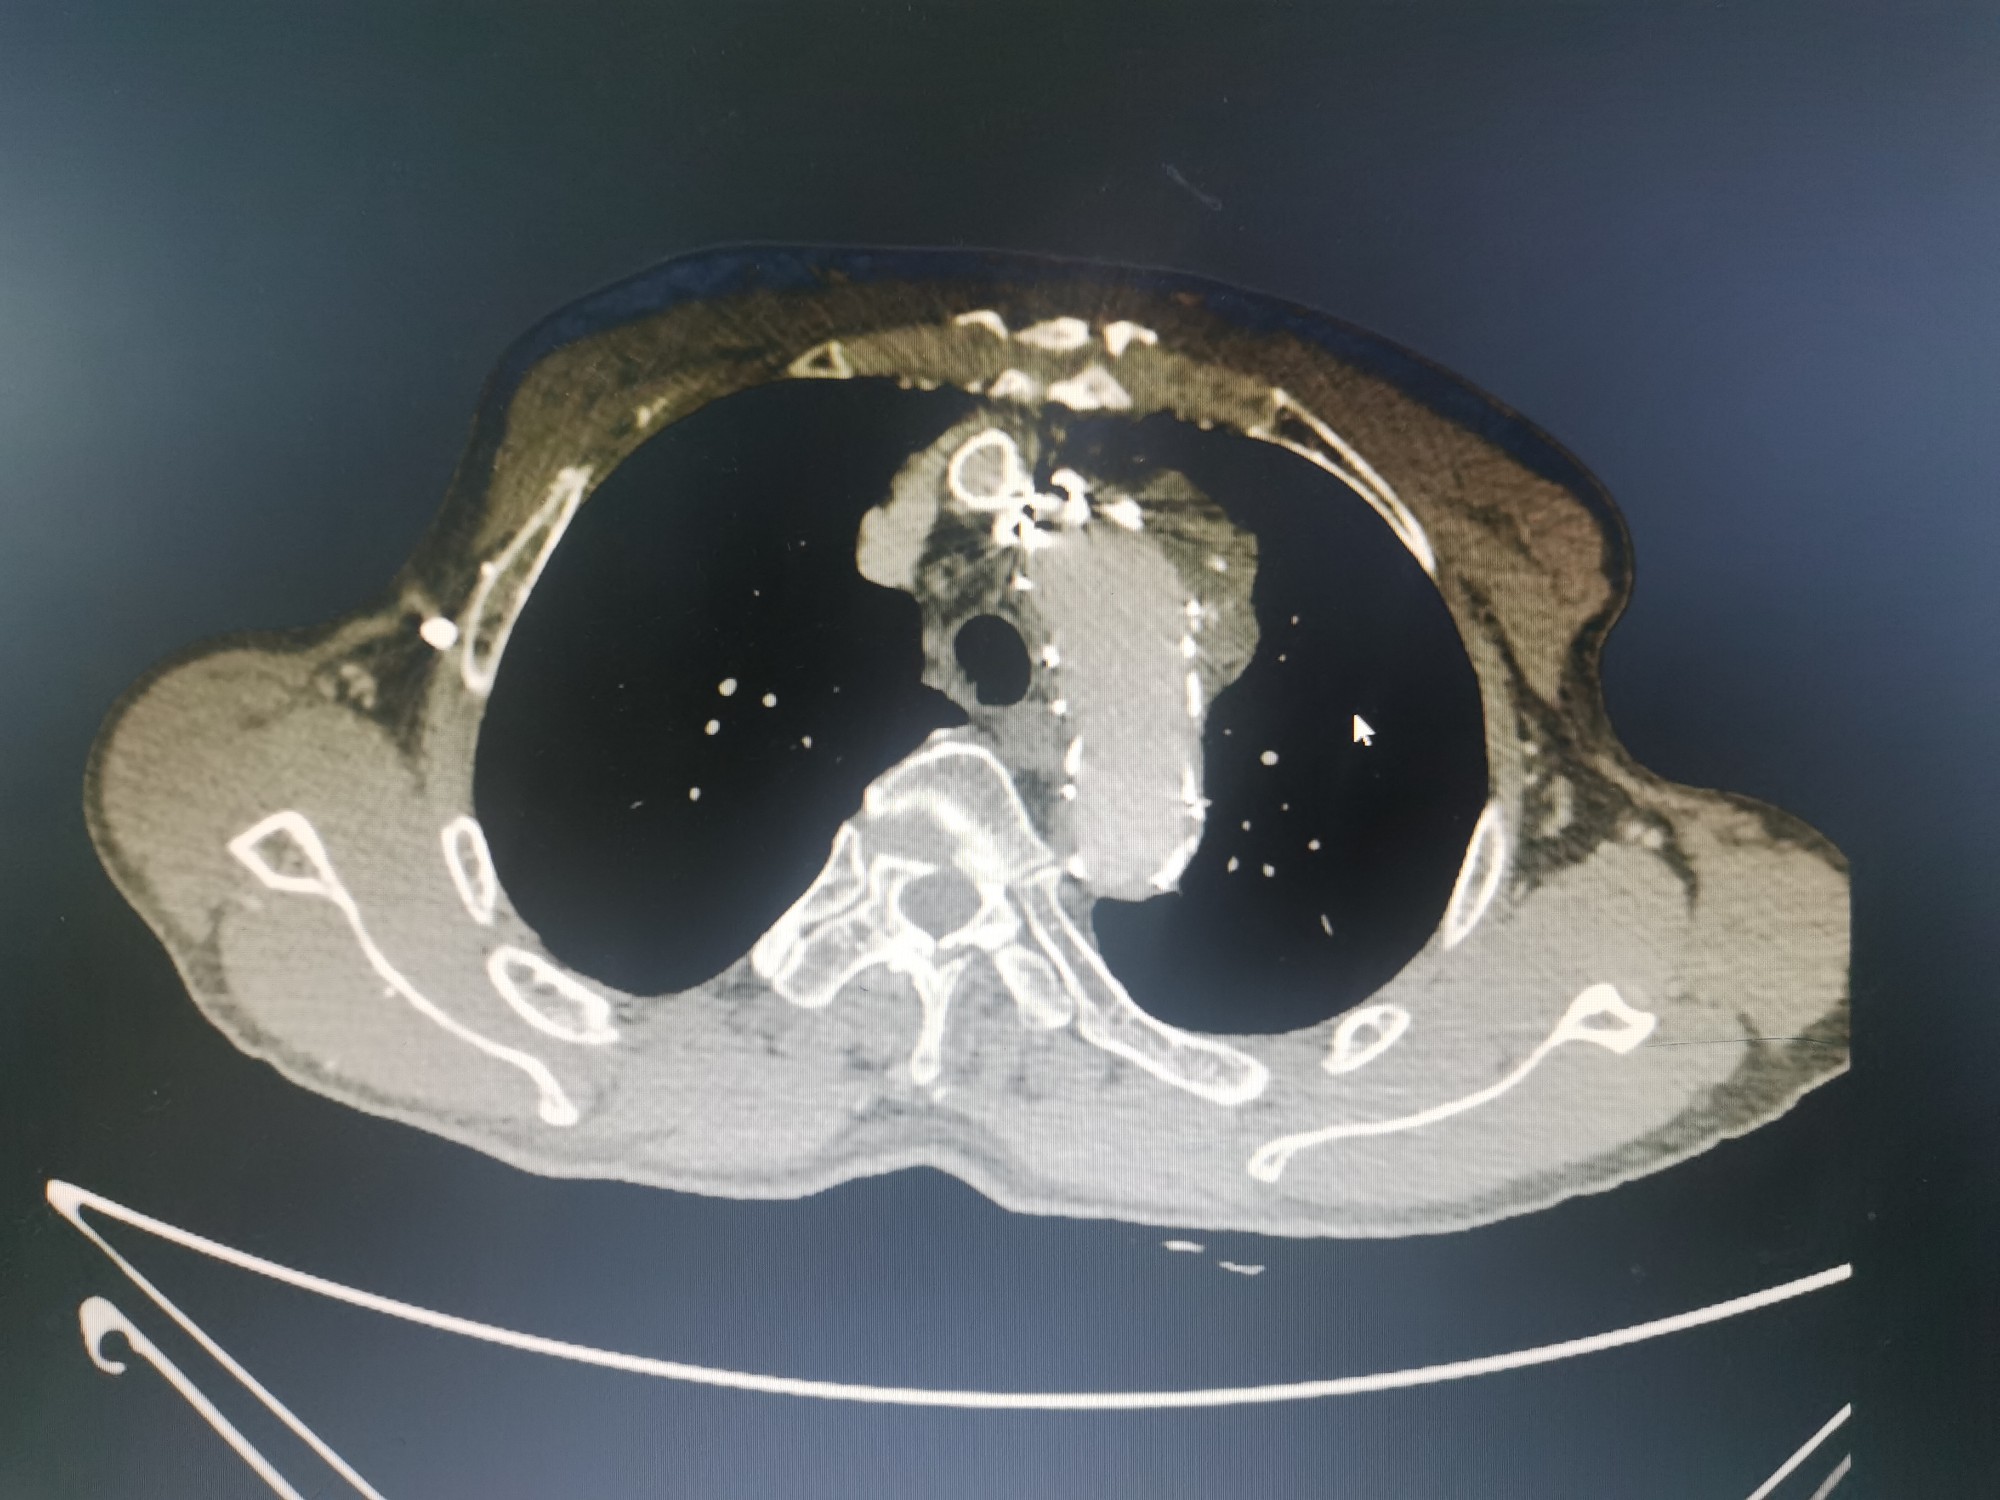

术后CTA